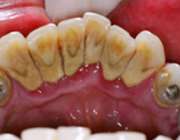

مجموعه پلاک میکروبی و جرم‌ها باعث می‌شود که عفونت لثه‌ای تشدید شود و به دنبال آن لثه اطراف ریشه دندان تحلیل برود، یعنی بیماری لثه به دنبال شکل‌گیری مجموعه‌ای از میکروارگانیسم‌ها، میکروب‌های اسید دوست، پلاک میکروبی و جرم به وجود می‌آید که در مکان شکل‌گیری این مجموعه، التهاب و ورم لثه را خواهیم داشت و در ادامه به صورت چرکی شدن لثه خود را نشان می‌دهد که این را پیوره می‌گویند.

از آنجا که لثه محافظ ریشه دندان است و ریشه دندان را احاطه کرده است، اگر لثه تحلیل برود، نسبت طول تاج به ریشه تغییر می‌کند. بنابراین طول تاج بیشتر خود را نشان می‌دهد، چنانچه در افراد مسن دندان‌هایشان بلندتر دیده می‌شود، چرا که لثه تحلیل رفته است.

تحلیل لثه سبب لق شدن دندان‌ها می‌شود، چرا که استخوان اطراف دندان تحلیل می‌رود. بنابراین دندان خیلی راحت لق شده یا می‌افتد.